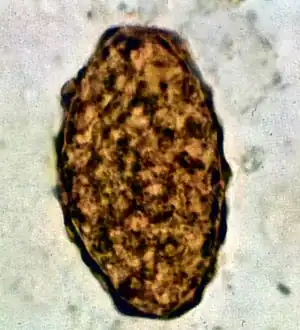

- Fertile egg as can be seen in a microscope

- Infertile egg

Ascaris lumbricoides is characterized by its great size. Males are 2–4 mm (0.08–0.2 in) in diameter and 15–31 cm (5.9–12 in) long. The male's posterior end is curved ventrally and has a bluntly pointed tail. Females are 3–6 mm (0.1–0.2 in) wide and 20–49 cm (7.9–19 in) long. The vulva is located in the anterior end and accounts for about one-third of its body length. Uteri may contain up to 27 million eggs at a time, with 200,000 being laid per day. Fertilized eggs are oval to round in shape and are 45–75 μm (0.0018–0.0030 in) long and 35–50 μm (0.0014–0.0020 in) wide with a thick outer shell. Unfertilized eggs measure 88–94 μm (0.0035–0.0037 in) long and 44 μm (0.0017 in) wide.[9]